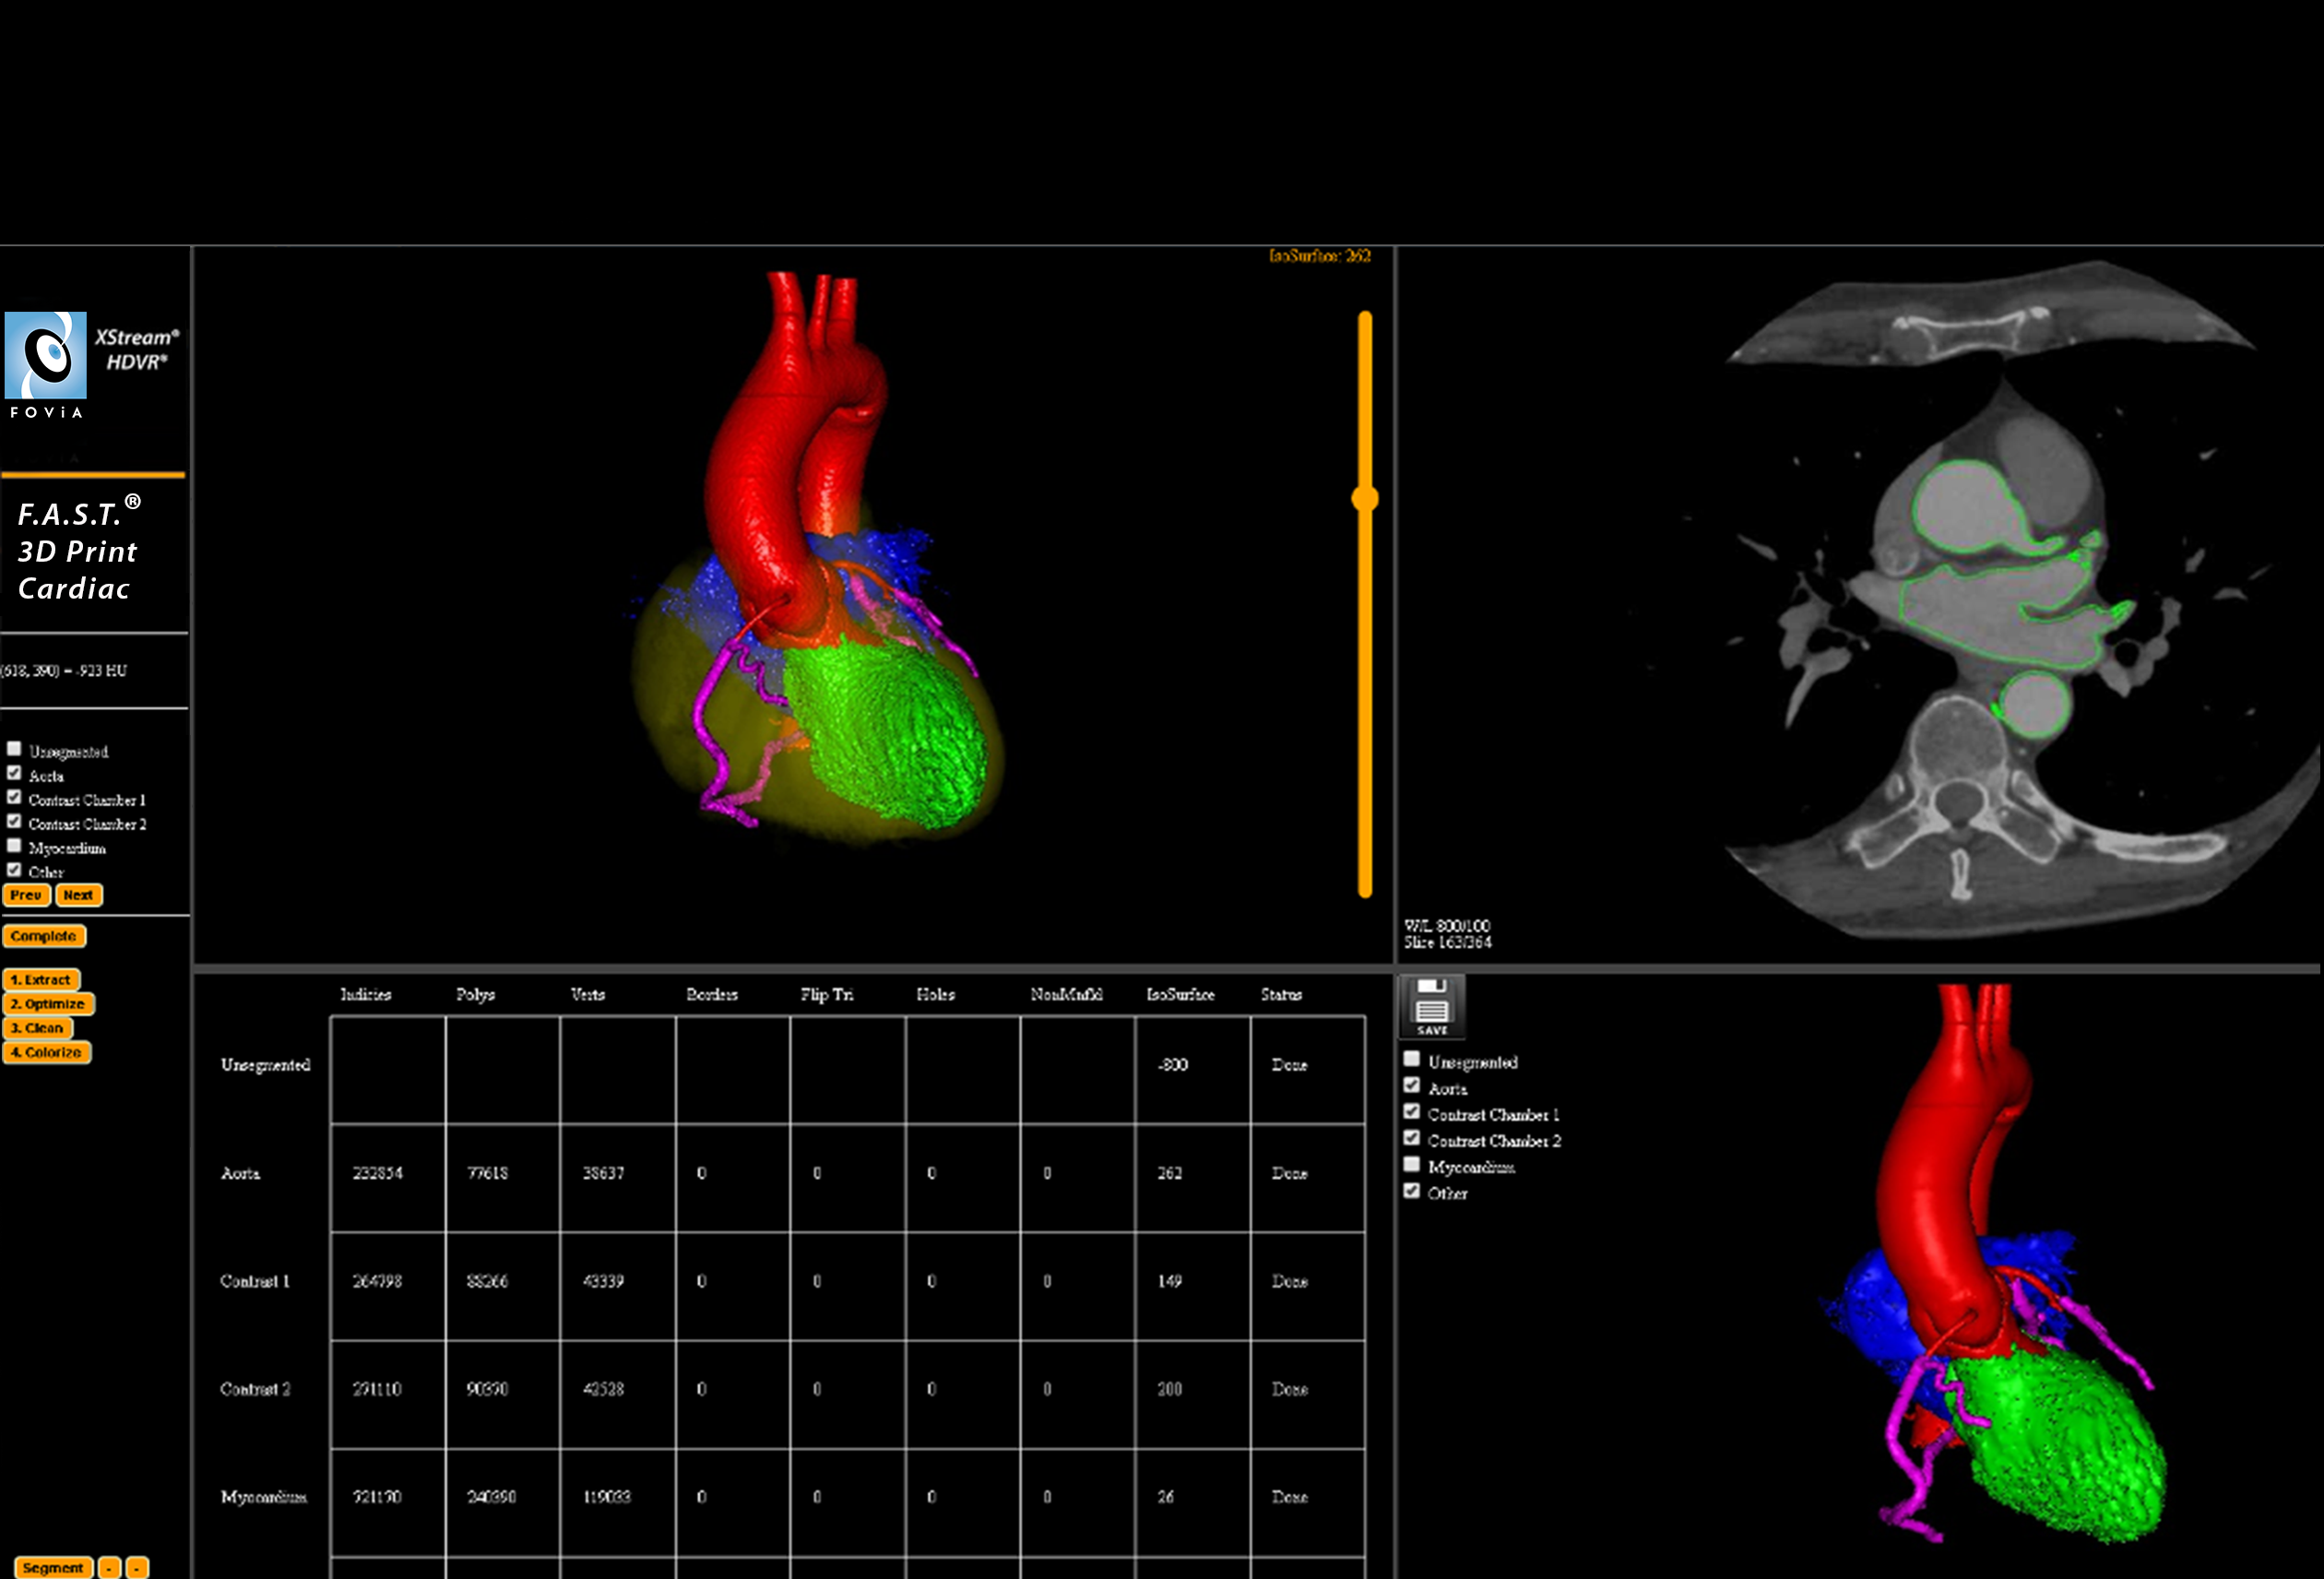

F.A.S.T. 3D Print Cardiac Workflow

F.A.S.T. 3D Print Cardiac Workflow